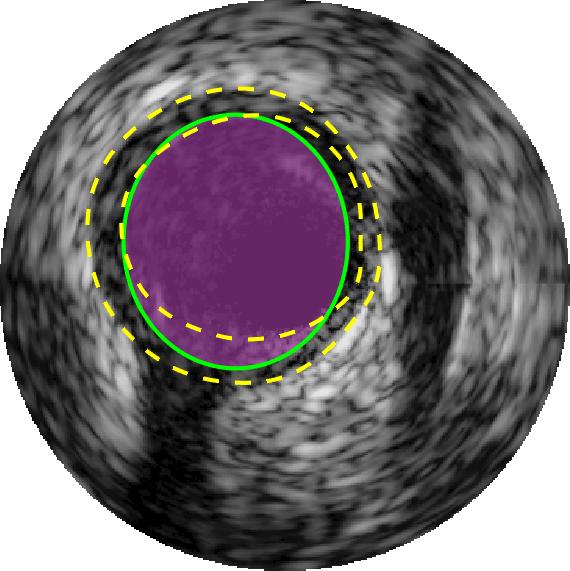

Qualitative evaluations are illustrated in Figure 4 and show the successful segmentation results of the proposed EREL selection strategy for 20 IVUS frames. The lumen areas are highlighted by the magenta colour while the media regions are green. Also, the manually annotated contours for both lumen and media are drawn as yellow dashed lines. As we can see, the chosen frames contain a variety of lumen and media morphologies.